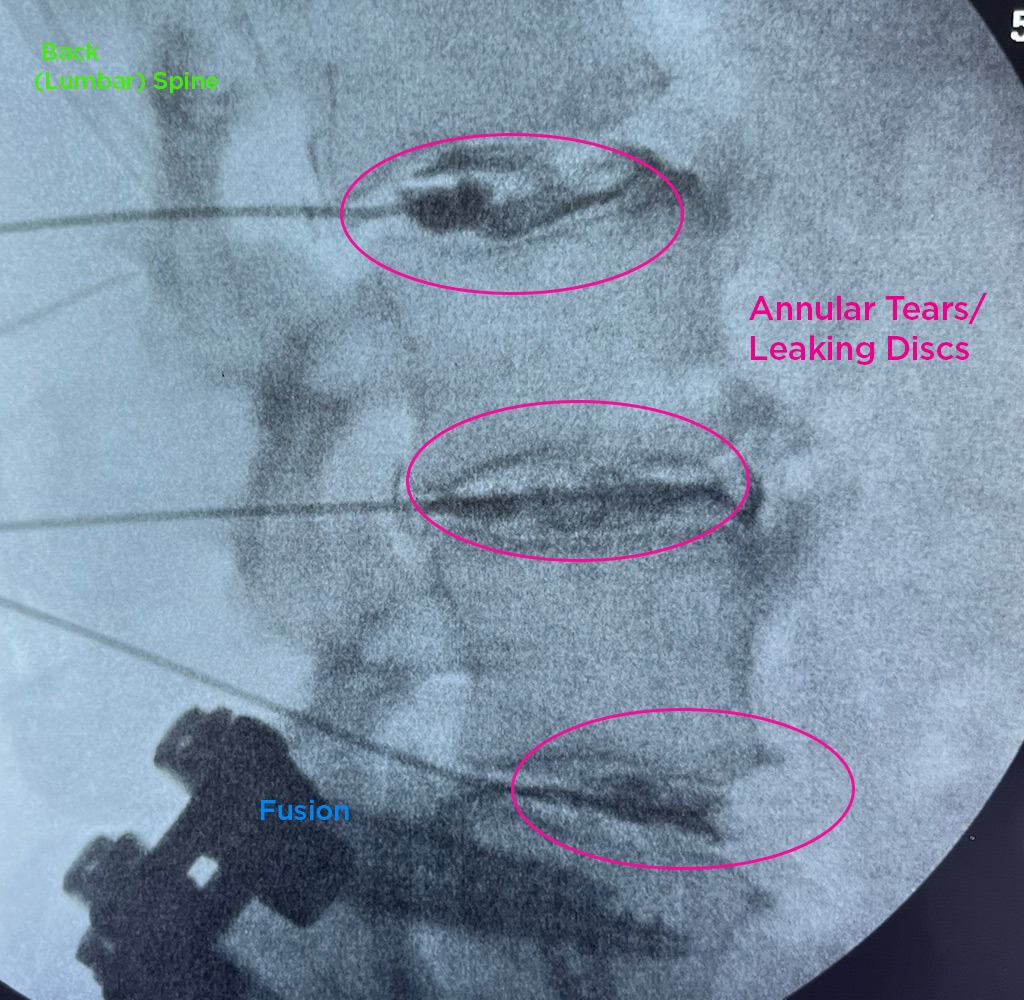

The Annulargram is a pain-free test and a crucial part of the DISCSEEL Procedure that identifies even the most subtle tears in spinal discs that MRI and discography cannot.

During the Annulargram, every disc in the region is tested to address current and future pain issues by finding even the most subtle annular tears. With the Annulargram, damaged spinal discs are pinpointed and precisely treated with Fibrin, leaving all healthy discs as they are.

Tears in spinal discs cannot be seen on MRI nor discography. As shown: leaky discs are only visible on the Annulargram.